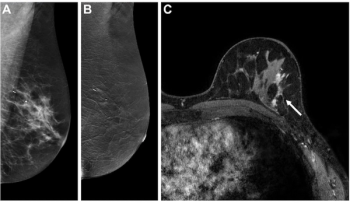

In a new study comparing standard breast MRI, abbreviated breast MRI and contrast-enhanced mammography in supplemental breast cancer screening, researchers found that MRI offered a greater than 14 percent higher cancer detection rate and a nearly 39 percent higher sensitivity rate than CEM.